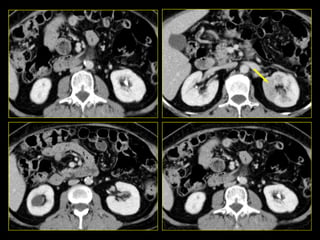

Caso # 9 ♀ , 35 años, con sospecha de proceso apendicular retrocecal por lo que se solicitó TC abdominal. Se realiza estudio en cortes axiales, se muestra la fase arterial, venosa y excretora.

FASE VENOSA FASE EXCRETORA FASE ARTERIAL

Hallazgos Caso # 9: Hay áreas hipodensas en el polo superior del riñón derecho, de aspecto triangular, las cuales se hacen evidentes en las diferentes fases del estudio, están en relación con proceso inflamatorio focal del riñón.